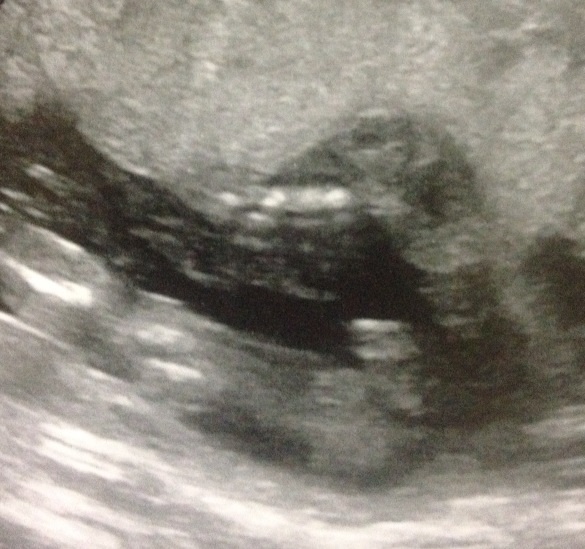

19 week scan. Is this really a boy?